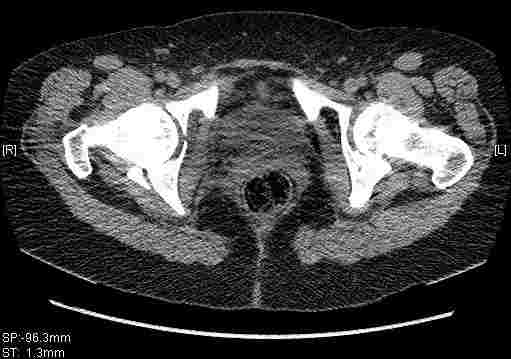

Удалось сегодня вывести пациентку в соседнюю больницу, где есть кт. Срезы сделаны только горизонтальные.

|

Приветствую,Антон.Рункова рядом нет,но после полученных данных КТ,обсуждали совместно.Итог обсуждения-развернутый ответ дать не получится,т.к.срезы выбраны не информативные.Если ориентироваться на данные 3D,то ,ИМХО,можно лечить на вытяжении.